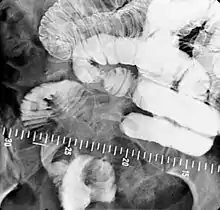

Barium meal examination showing the stomach and duodenum in double contrast technique with CO2 as negative contrast medium

• Barium meal examinations are used to study the lower esophagus, stomach and duodenum.[2]

Intravenous injection of Buscopan (Hyoscine butylbromide) 20 mg or glucagon 0.3 mg is used to distend the stomach and slow down the emptying of the contrast into the duodenum.[13]

Right anterior oblique (RAO) view is used to demonstrate antrum and greater curve of stomach. Supine position is to demonstrate antrum and body of stomach. Left anterior oblique (LAO) view is used to see the lesser curve of stomach en face. This position is also used to check for gastroesophageal reflux when patient is asked to cough or swallow (water siphon test). Left lateral tilted with head up 45 degrees is used to demonstrate the fundus of the stomach.[13] To demonstrate the duodenal loop, the subject can lie down in prone position on a compression pad to prevent excessive barium flowing into the duodenal loop. Anterior view of duodenal loop can be seen at RAO position.[13] Duodenal cap can be visualised by taking images when subject lie down in prone position, RAO, supine, and then LAO positions or it can be seen on erect position with RAO and steep LAO views.[13] Total mucosal coating of the stomach is done by asking the subject to roll to the right side into a complete circle until RAO position. Arae gastriae in the antrum (fine reticular network of grooves) is visible if good coating is achieved.[13]